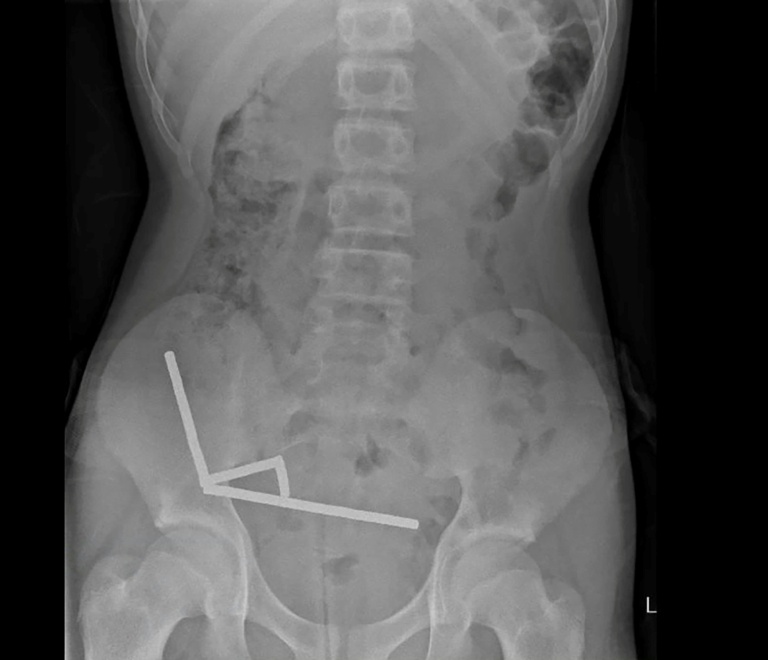

According to a report published in the New Zealand Medical Journal, the boy revealed he ingested approximately 80 to 100 neodymium magnets, each measuring 5×2 mm, about a week prior to his hospital visit. The magnets have been banned in New Zealand since January 2013 due to safety concerns. An X-ray indicated that the magnets had clumped together in four distinct lines within the child’s intestines, creating pressure that led to tissue death, known as necrosis, in four areas of his small bowel and caecum.